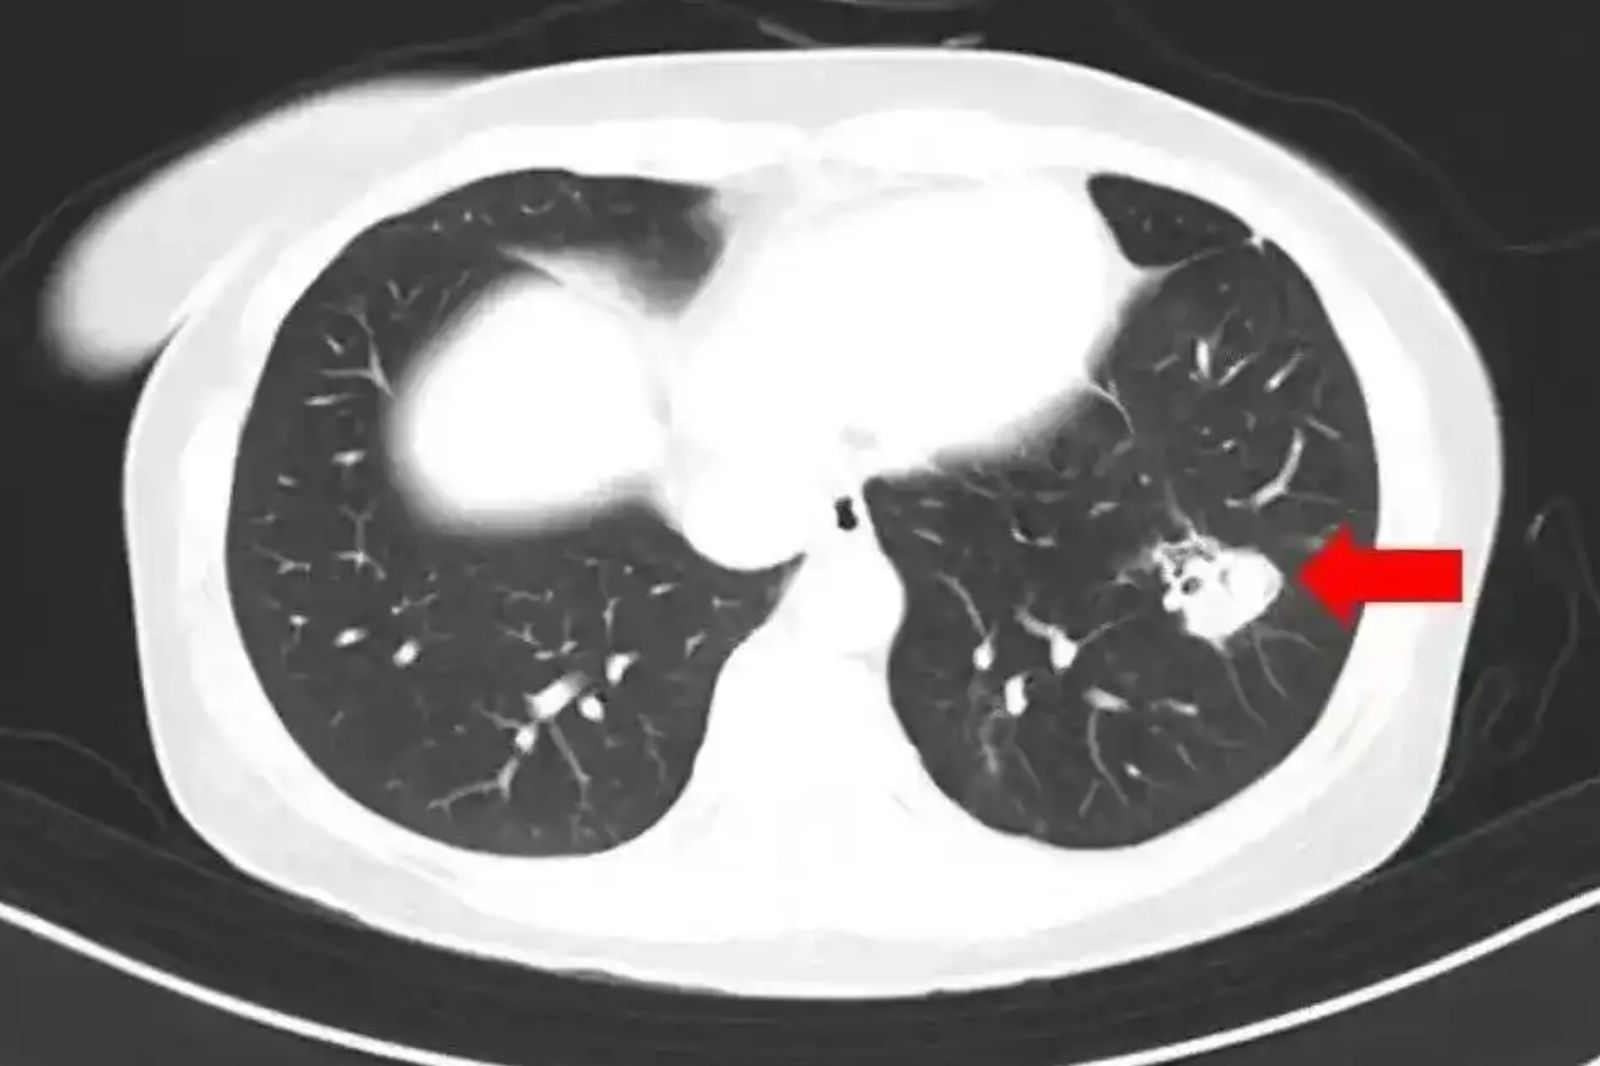

為了進一步釐清病情,醫生幫沈女進行纖維支氣管鏡檢查、肺泡灌洗液病原體檢測,果然發現氣道壁上有大量白色菌斑,化驗後確認是麴黴菌。

報導指出,麴黴菌是一種真菌,被世界衛生組織列為1級致癌物質,其毒性是砒霜的66倍。它廣泛存在於自然界中,主要以枯死植物、動物排泄物及屍體為營養源。人體如果在免疫力較弱時,麴黴菌進入了肺部,就可能引起沈女這樣的病情──肺麴菌病。